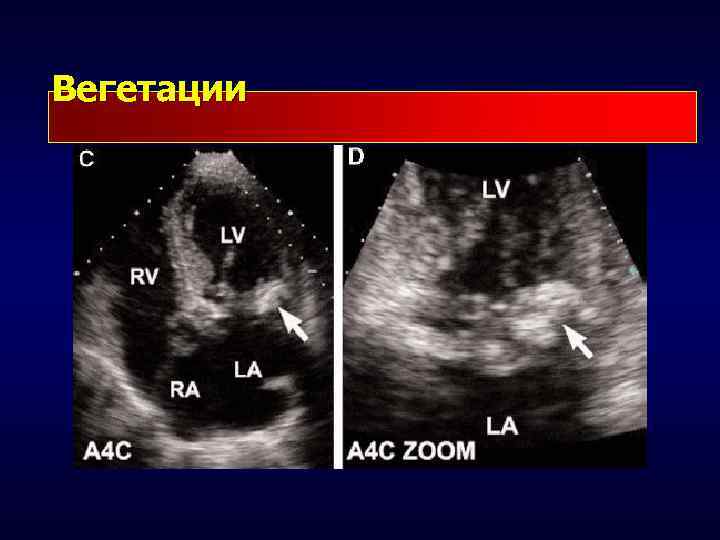

Вегетации

Вегетация • Подвижное, неправильной формы образование с неровными контурами, прикрепленное к клапанам • Размер от нескольких мм до нескольких см • Располагается обычно на поверхности клапана, обращенной в сторону низкого давления • Может пролабировать через клапан вместе с потоком крови